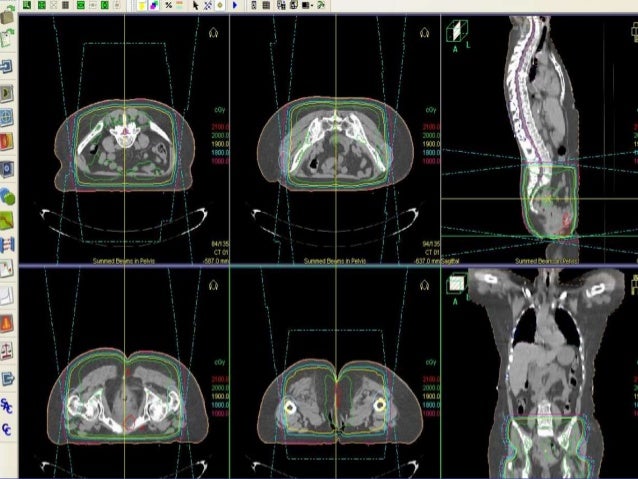

22. 22. Single Vs Multi-Fraction

23. 23. SYSTEMATIC REVIEW

24. 24. Single fraction v multifraction more convenient less costly shorter time with acute side effects fear of high doses per fraction higher retreatment rate( 2-2,5 times higher) concern about toxicity in long-term survivors flare of bone pain maybe be higher